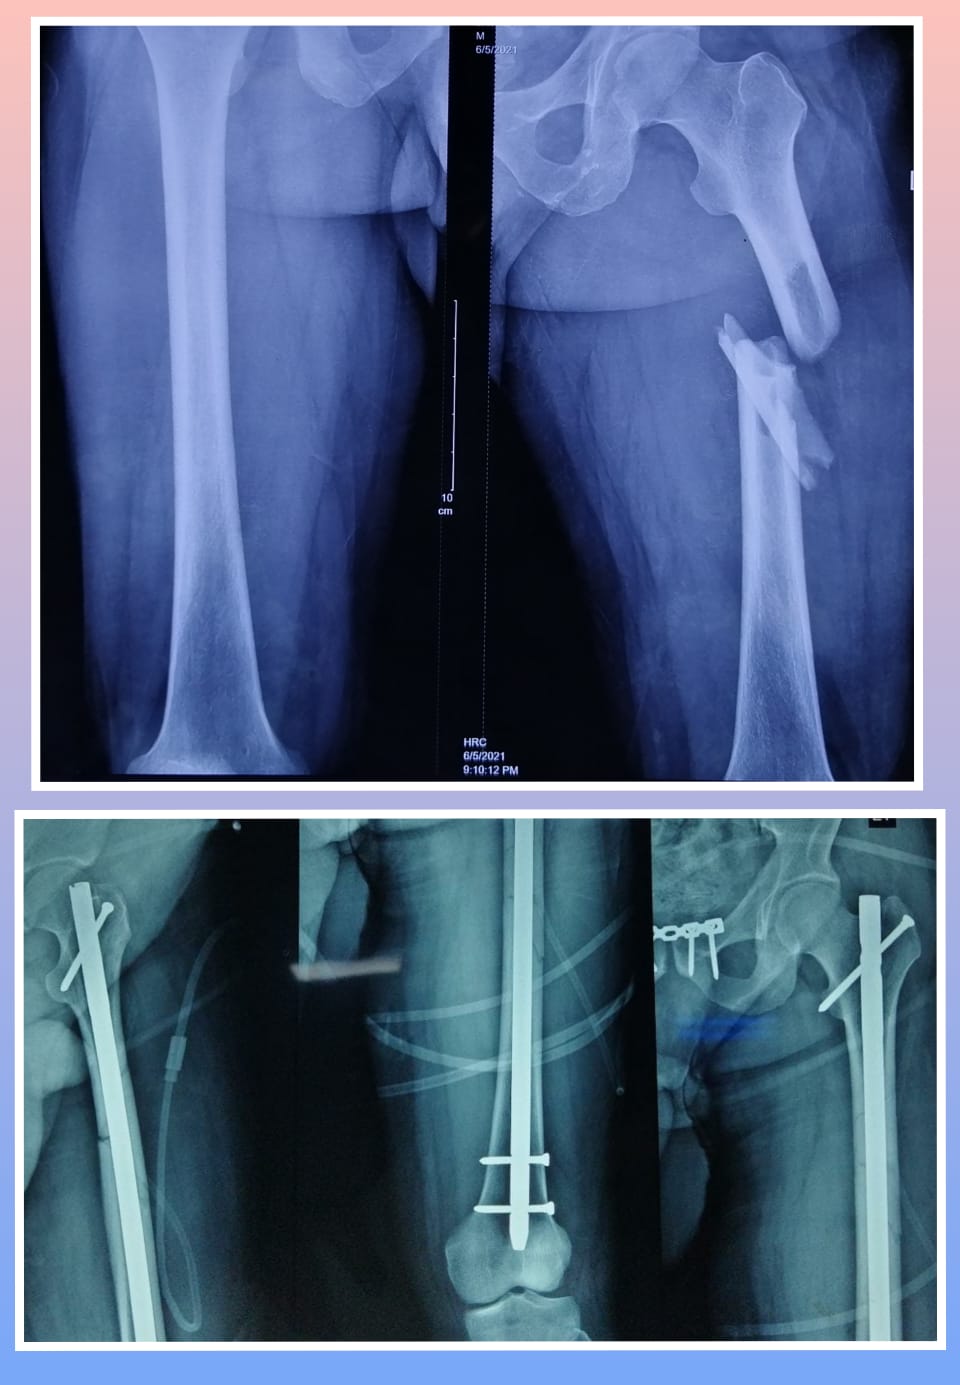

X-ray

Warning: Graphic Content

The following section contains graphic images of surgical procedures. These images are intended for educational purposes and may be disturbing to some viewers. Viewer discretion is advised.

Surgeries